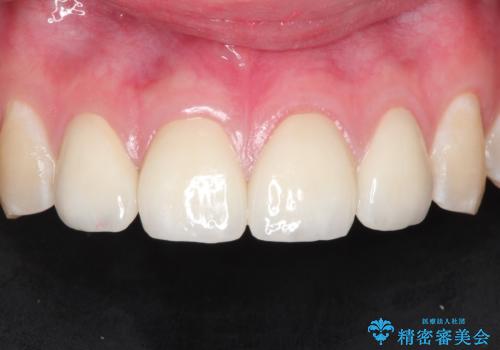

まだらな色の前歯をきれいにしたい セラミック治療による見た目の改善

- 前歯をきれいにしたいとのご希望がありました。

生まれつき歯の色が白濁しているところや、黄色くなっているところがあり、セラミッククラウンに審美的改善を行うこととしました。

ご自身の歯を削る必要がありましたが、セラミッククラウンを装着することで、審美的改善ができました。